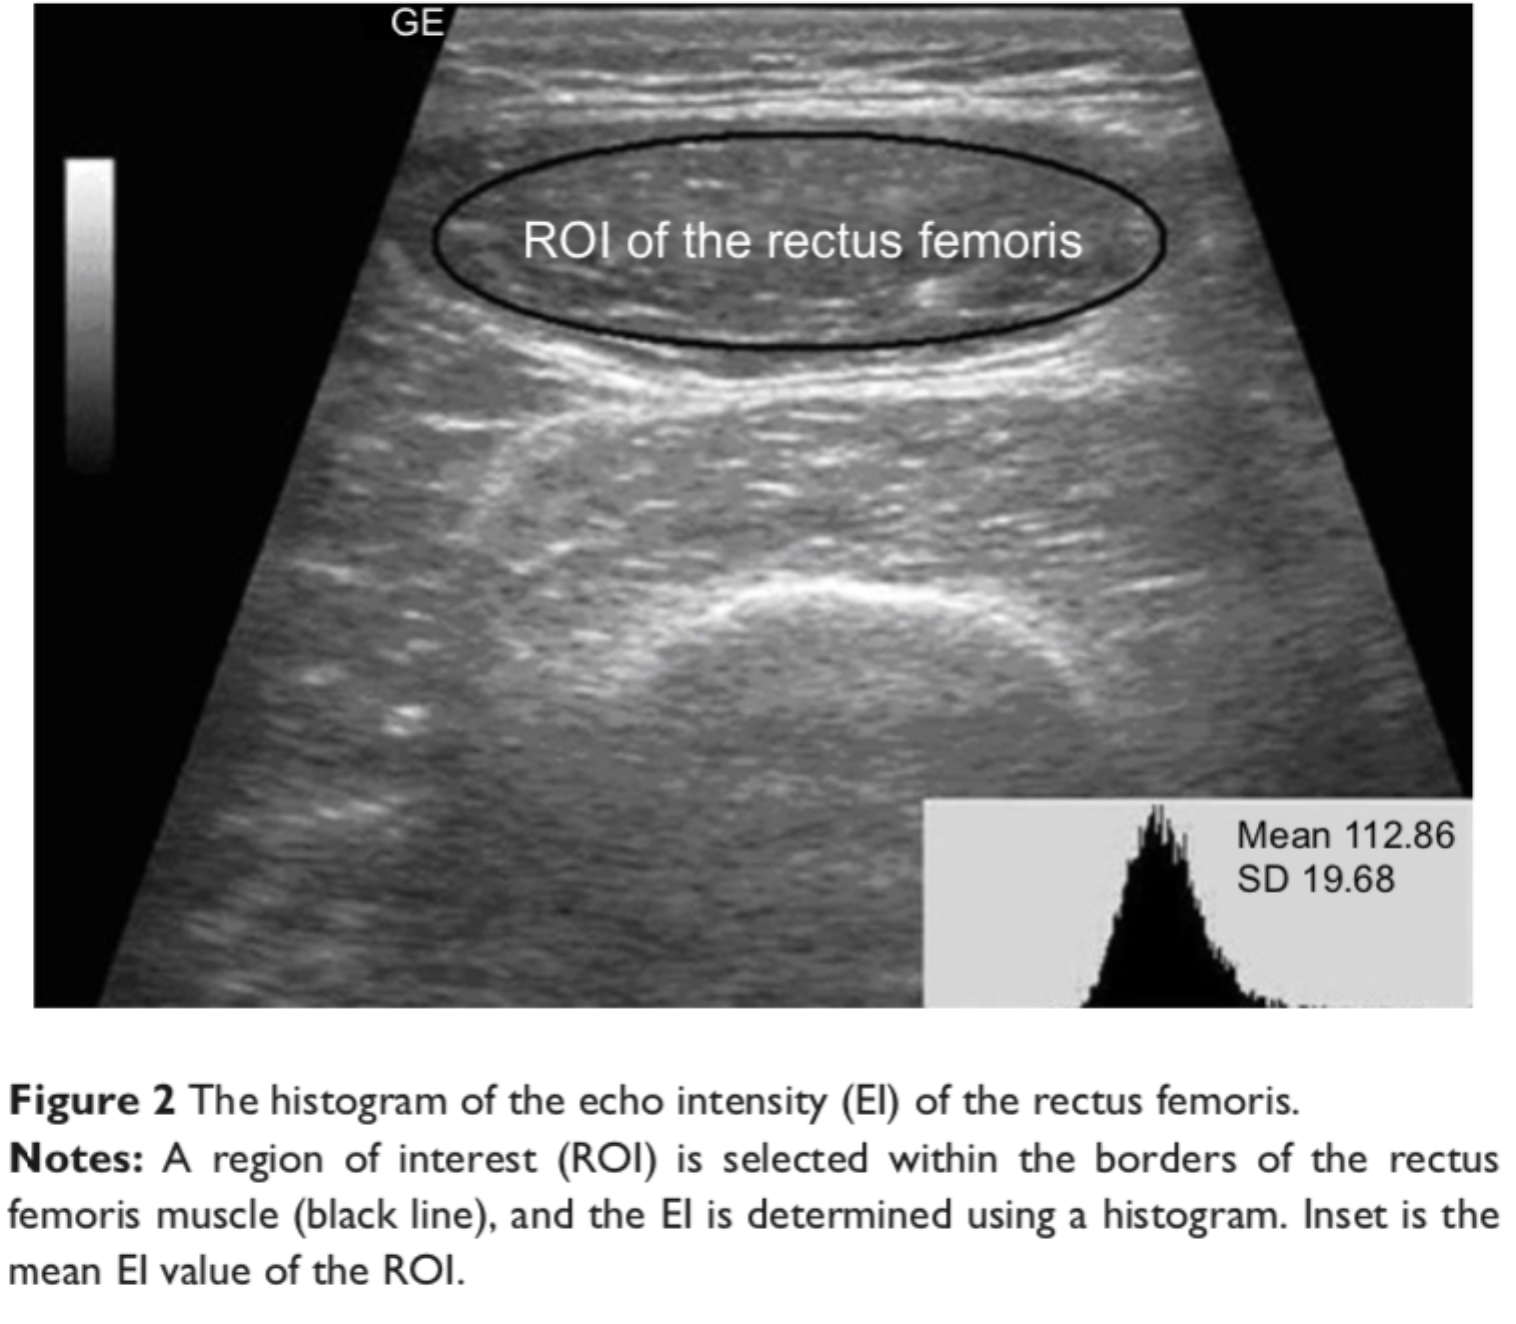

叶熊博士潜心于教学和自然科学研究,不忘初心、默默耕耘。分别主持厅局级和省部级项目各1项,校级项目3项,总资助经费30万元,发表第一作者SCI论文3篇,累计影响因子11.133分。于2017年10月,在《Int J Chron Obstruct Pulmon Dis》杂志(IF:3.355)发表题为“Echo intensity of the rectus femoris in stable COPD patients”的研究论文1篇,该研究探索了一种超声图像回声强度定量方法,用于评估慢性阻塞性肺病患者股四头肌功能,有助于早期诊断慢性阻塞性肺病患者的骨骼肌功能失调;于2021年5月,在《Frontiers in Medicine》杂志(IF:5.091)发表题为“A Novel Normalized Cross-Correlation Speckle-Tracking Ultrasound Algorithm for the Evaluation of Diaphragm Deformation”的研究论文1篇,该研究首次把互相关归一算法用于膈肌超声斑点追踪,为研究膈肌动力学提供了一种创新性的方法。该成果是叶熊老师和清华大学生物工程系罗建文研究员团队合作的阶段性成果